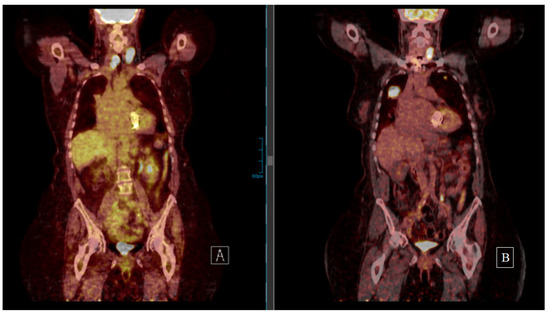

There is one (8.3%) incomplete response (I.R.) with elevated Tg without structural disease, two (16.6%) stable disease (S.D.) cases, whereas all other patients showed slow progress during last follow-up. Patient 4 was lost to follow-up after 6 months. Among the eight (66.7%) patients receiving both surgery and EBRT, only patient 6 and 8 had no further cervical recurrence after the repeated surgical resection. In the other six (75%) cases, the cervical relapse recurred again despite surgery and EBRT (Figure 2).

Figure 2.

Patient 5 underwent resection of a cervical FTC recurrence diagnosed 5 years after thyroidectomy despite bilateral lung metastases (18F-FDG PET on the left side (A)). Cervical and thorax EBRT were performed. The 18F-FDG PET on the right (B) (5 years after the second cervical resection and 10 years after first FTC diagnosis) shows both cervical and lung progress. After thorough patient information concerning the evidence on tyrosine kinase inhibitors, the patient refused treatment and was progressing at last follow-up.